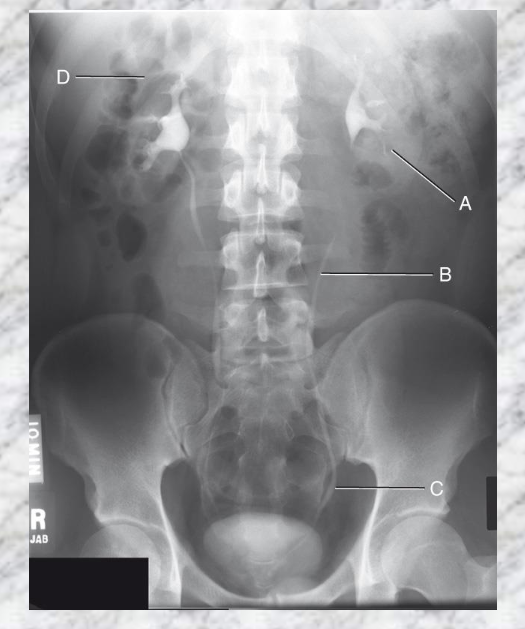

A. Left Kidney

B. Left Ureter

D. Adrenal glands